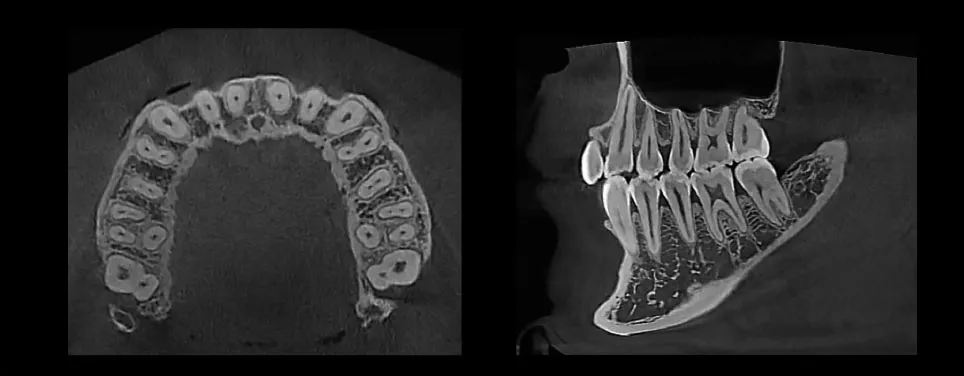

3D Imaging

MAX 18 x 16.5 cm FOV, perfect for capturing dentition, sinus, or TMJ

Expansive FOV (Max 18×16.5cm)

18×16.5 cm FOV allows diagnosis for most maxillofacial structures

Minimized Metal Artifacts

PrecisionMAR (Metal Artifacts Reduction) allows for greater diagnostic accuracy by significantly reducing metal artifact

Superior Image Quality

Striking contrast and sharpness of images produced by HDX WILL’s image reconstruction technology